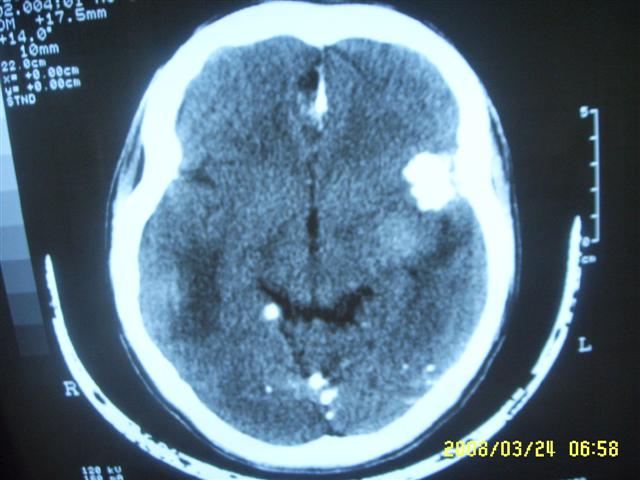

以下是引用dyqct在2008-4-2 20:09:00的发言:[br]考虑为:神经纤维瘤病(nf1型)。建议增强进一步检查。